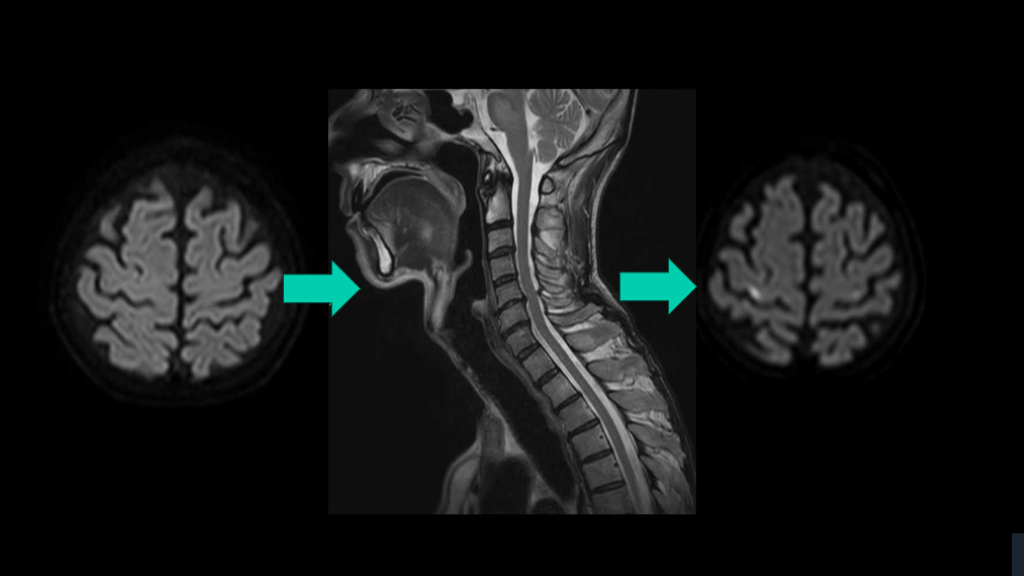

脊髄障害は、 悩むならwhole spine MRI 矢状断をとっておく。 TIPS

CASE 70歳女性例。突発発症の下肢対麻痺である。 先ほどのアイデアのごとく、4つの鑑別をまずは挙げる。 そして、MRIではどこを撮るのか?は正直、難しい。 正直、かっこつけずに、whole spine MRIでよいと思う。

脊髄障害の初手はwhole spineでよい。 脊髄緊急疾患でのWhole spine-MRIは推奨。 ER脊髄障害S/Oで、約半数の症例の脊髄緊急疾患診断に有用だった。 特に、外傷、麻痺、および排便/排尿症状患者で価値ある可能性 解説 Curr Probl Diagn Radiol. 2021;50:637-645. Handb Clin Neurol. 2017:140:319-335.

脊髄障害の初手はwhole spineでよい。 脊髄障害の高位診断は正直難しい。 症状の高位と実際の脊髄障害の高位は異なる。 実際の障害高位は、症状の高位よりも、より上にある。 対麻痺なら、腰髄レベルよりもより高位でどこでもあり。 腰髄レベルMRIのみ施行なら空振りリスクある。 それなら、WS-MRIの撮影でもよかろう。 解説